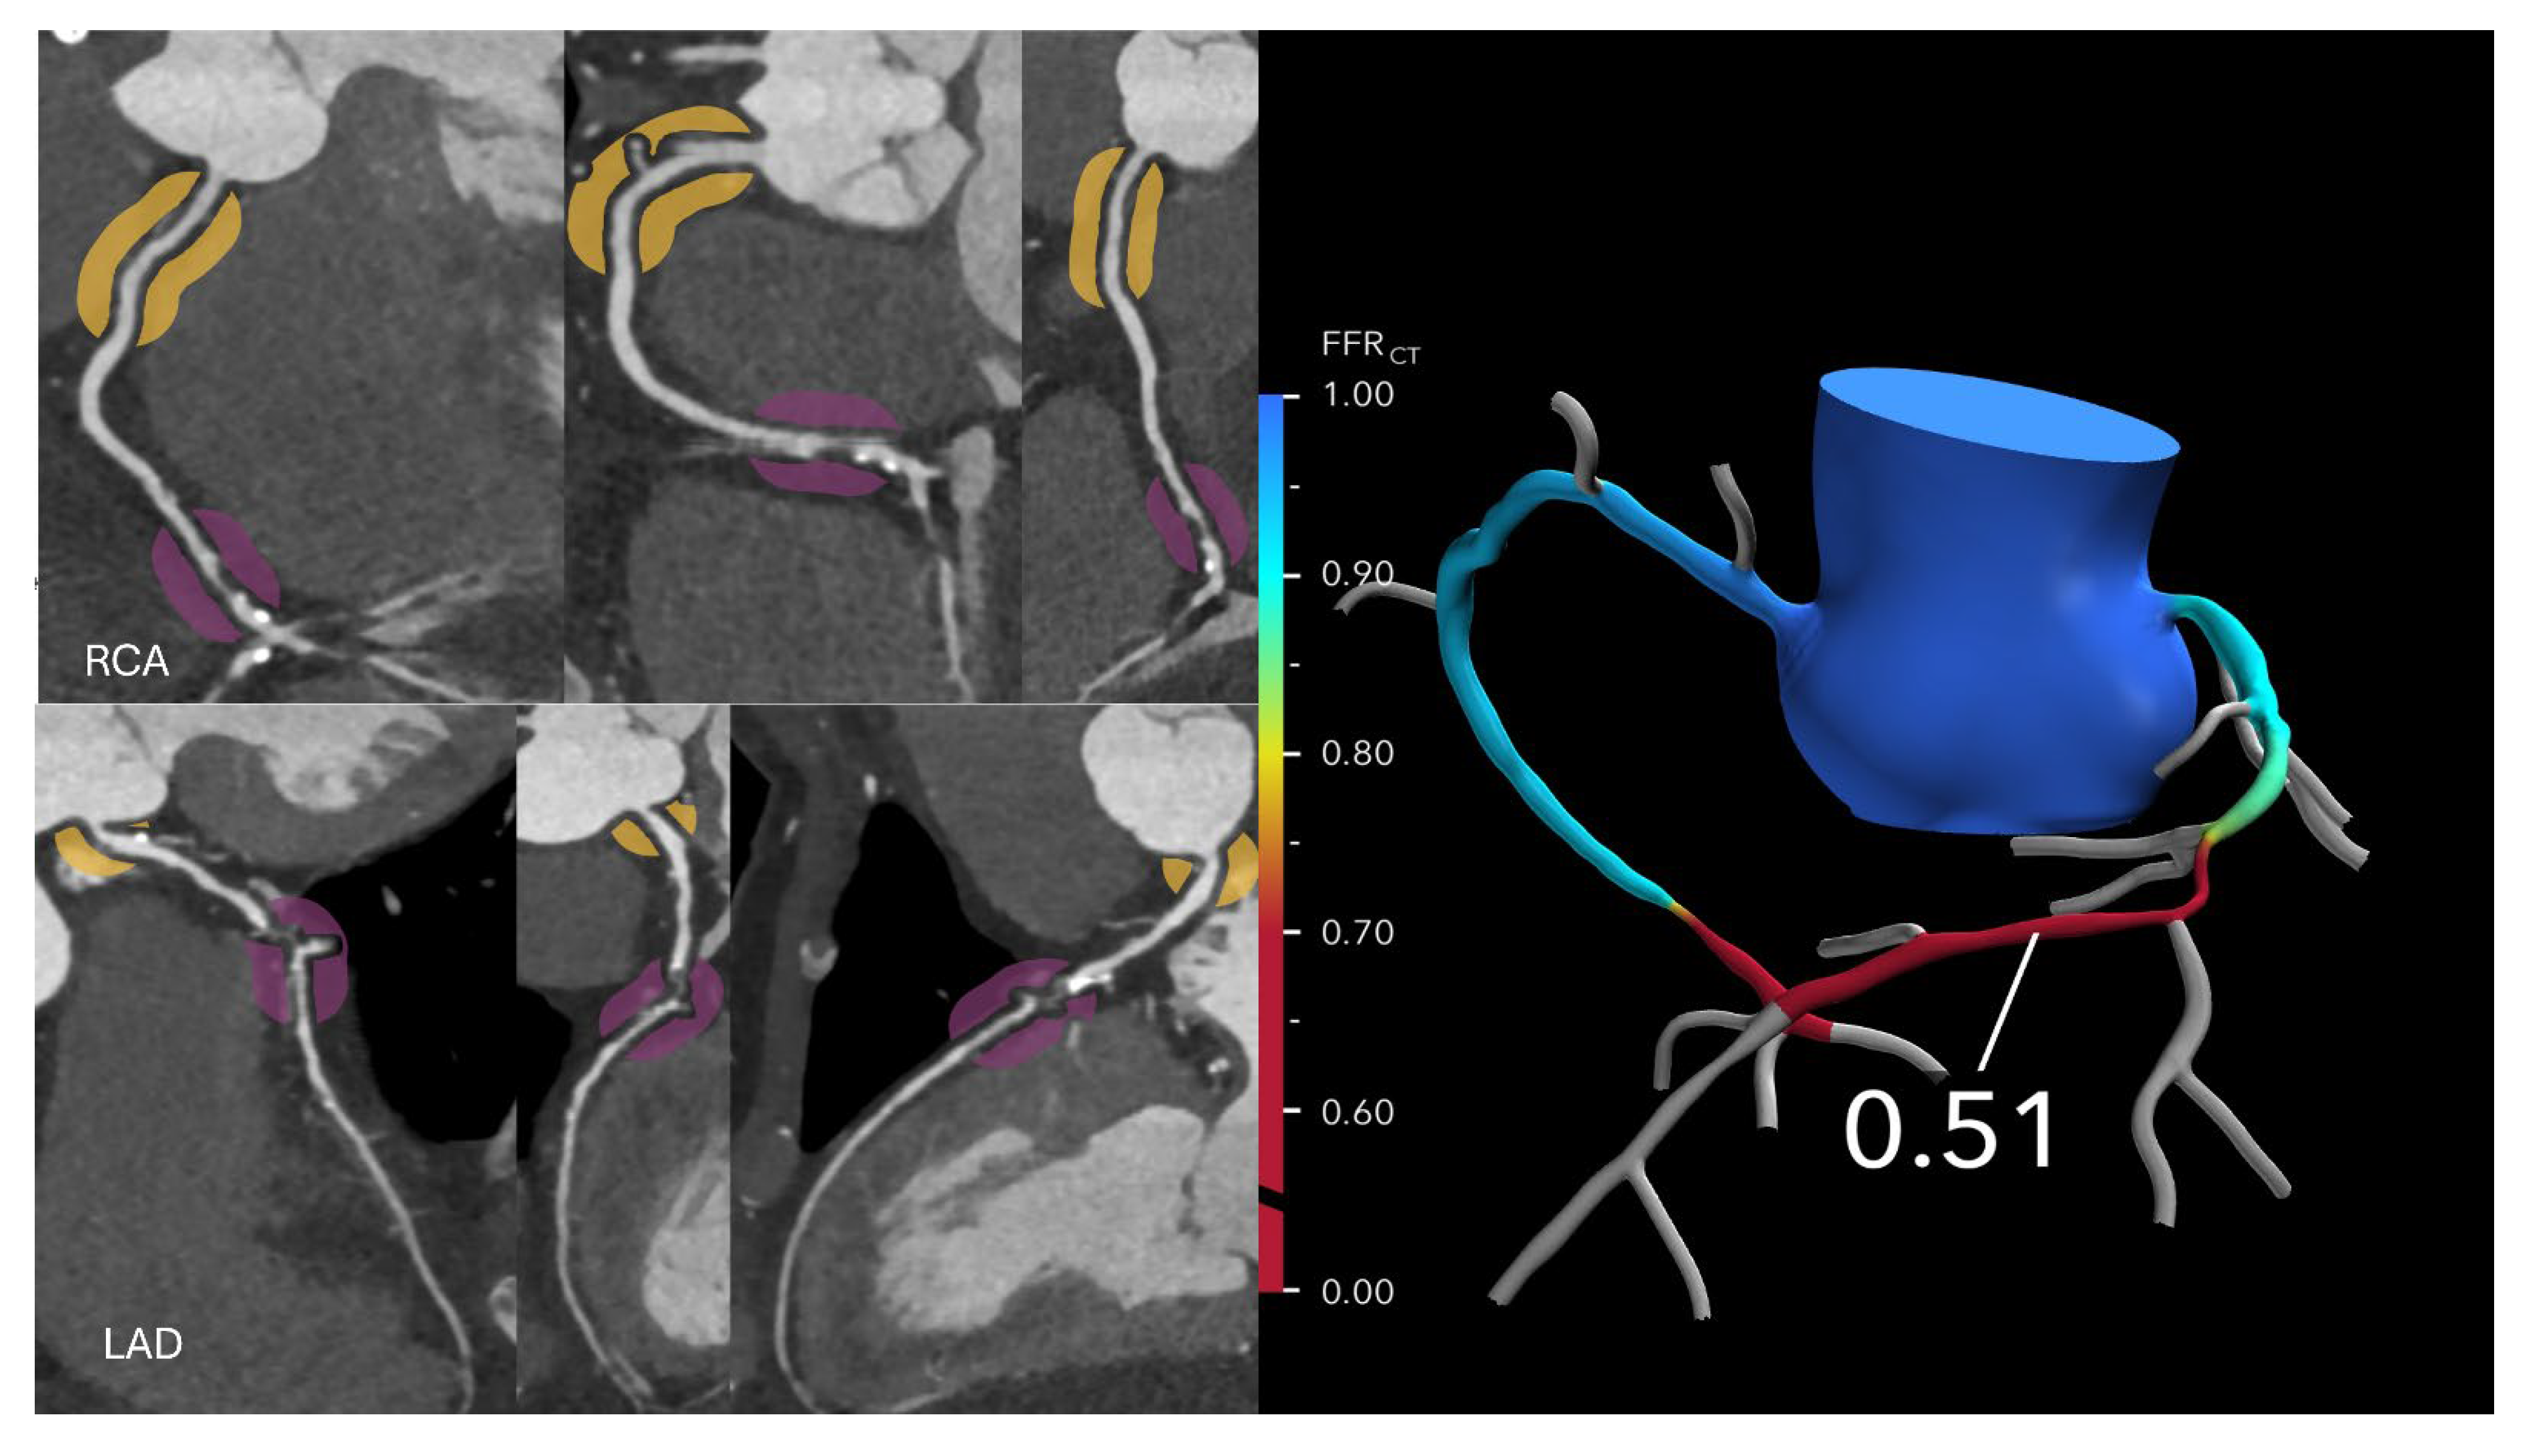

Figure 3. Optimizing treatment decisions with FFR-CT: (Left): A curved MPR coronary CTA image in a 64-year-old man with stable chest pain reveals severe stenoses in the mid left anterior descending (LAD) artery and distal right coronary artery. (Right): The corresponding FFRCT image shows a value of 0.51 measured 2 cm distal to the lesion, indicating severely reduced flow. Based on these findings, the patient proceeded to invasive coronary angiography followed by intervention.